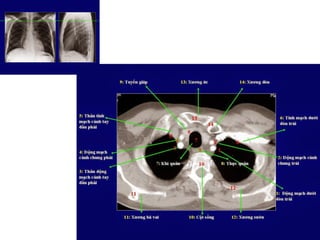

Giải phẩu CT ngực – các mạch máu

lớn.

SVC: tĩnh mạch chủ trên.

Aortic arch: cung đm chủ

Pulmonary artery: đm phổi

Main sterm bronchus: phế quản gốc

63